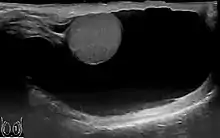

Through diagnostic ultrasound the accumulation of fluids can be diagnosed correctly.